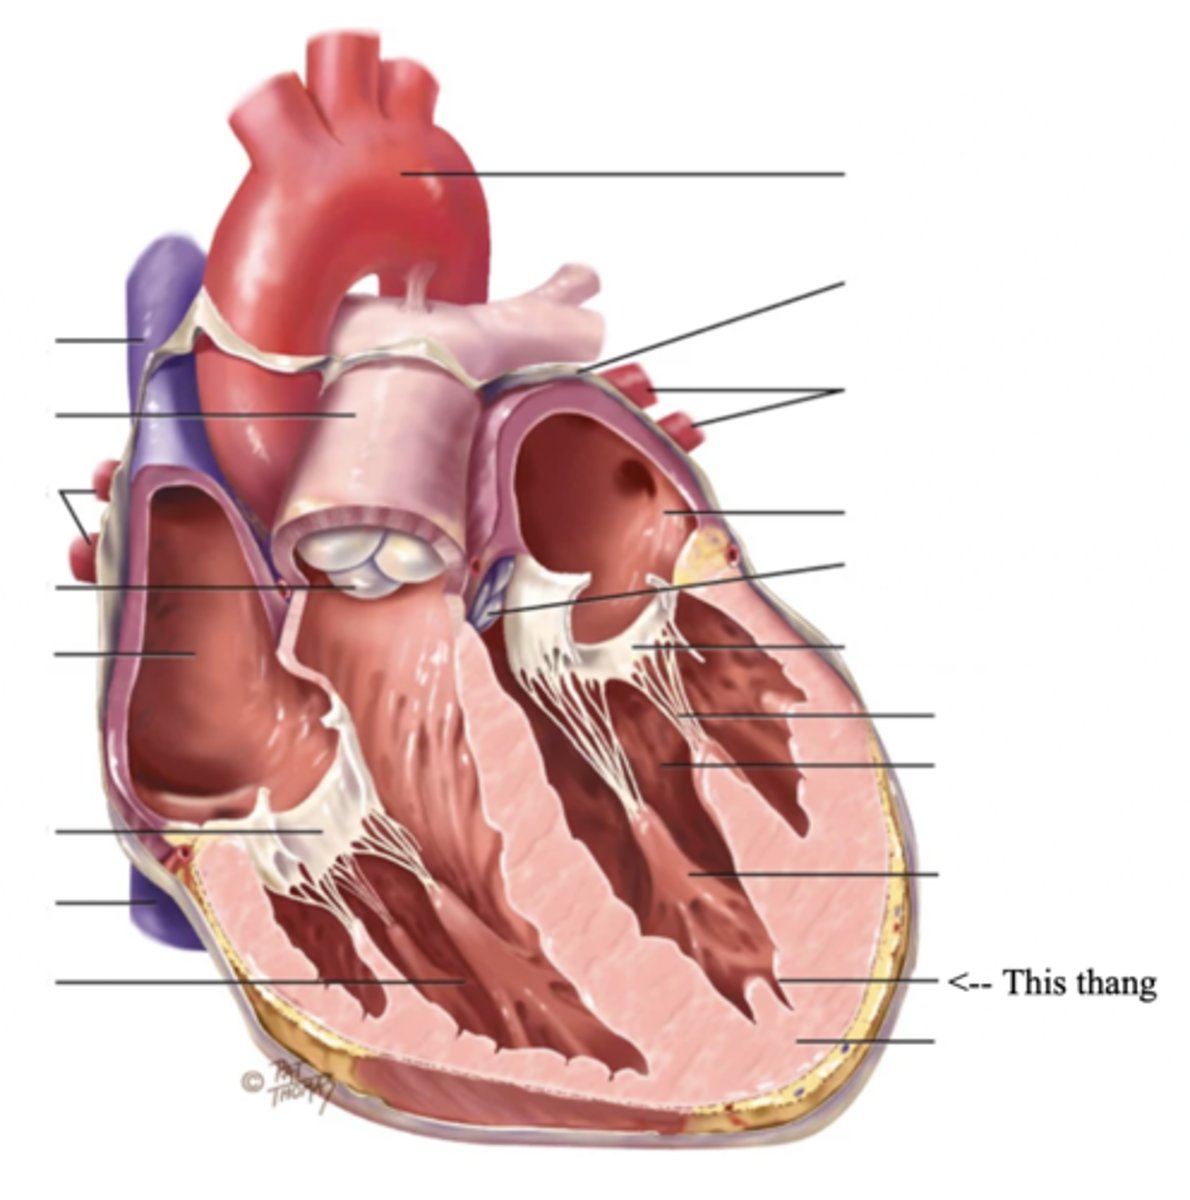

Anatomy of the Heart

3 Layers of the Heart Wall

- Pericardium

- Myocardium

- Endocardium

Pericardium

Myocardium

The muscular wall of the heart; does the pumping

Endocardium

The thin layer of endothelial tissue that lines the inner surface of the heart chambers and valves

2 Types of Chambers in the Heart

- Atrium

- Ventricles

Atrium (2)

A thin-walled reservoir for holding blood, located at the upper chamber of the heart

Ventricle (2)

The thick walled muscular pumping chamber of the heart located at the bottom chamber of the heart

2 Main Types of Valves of the Heart

- Atrioventicular

- Semilunar

Atrioventricular Valves (AV) (2)

The valves that separate the atria and the ventricles

The 2 Atrioventicular Valves of the Heart

- Tricuspid

- Mitral

Tricuspid Valve

- The right AV valve separating the right atrium from the right ventricle

- Connected by 3 chordae tendinae

Mitral (Bicuspid) Valve

- The left AV valve separating the left atrium from the left ventricle

- Connected by 2 chordae tendinae

Chordae Tendinae

Fibers (heart strings) attatched to the tricuspid and mitral valve which pull it closed when papillary muscles contract, preventing back flow of blood

Semilunar Valves (SV) (2)

Valves located between the ventricles and the pulmonary arteries and aorta

The 2 Semilunar Valves of the Heart

- Pulmonic

- Aortic

Pulmonic Valve

The SV valve of the right side of the heart

Aortic Valve

The SV valve of the left side of the heart

The 4 Great Vessels of the Heart

- Superior/inferior venae cavae

- Pulmonary artery

- Pulmonary veins

- Aorta

Superior/Inferior Venae Cavae

The large veins that empty into the right atrium of the heart and return unoxygenated venous blood to the right side of the heart

Pulmonary Artery

Artery carrying oxygen-poor blood from the heart to the lungs

Pulmonary Veins

Veins carrying oxygenated blood from the lungs to the heart

Aorta

The largest artery in the body which carries oxygenated blood from the heart throughout the body